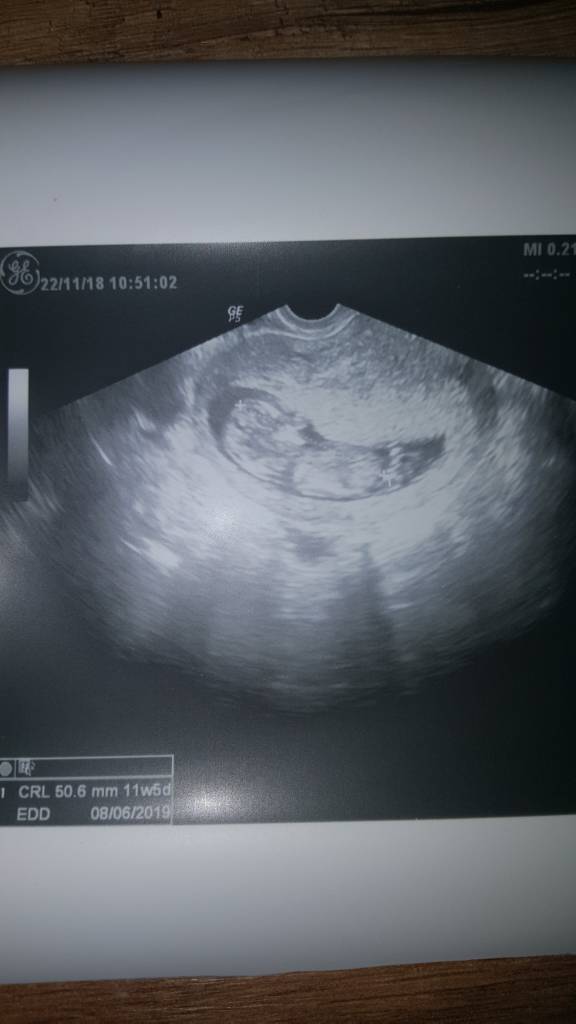

Ja już po wizycie, dzić ma już 5.6 cm, wszystko w porządku, leżał sobie ze skrzyżowanymi nogami wiec nie było nic widać. Według usg 11+5. Jakoś wyjątkowo spokojne te moje dziecko. Moje poprzednie fikały koziołki A ten grzecznie leży [emoji6]oby tak już zostało [emoji7] dostalam skierowania na badania krwi. Musze powtórzyć tsh i glukoze. 28.11 mamy prenatalne A 6.12 kolejna wizyta bo mi sie l4 konczy.

Ależ duży ten Człowieczek [emoji7][emoji7][emoji7] wstydzioszek [emoji39]